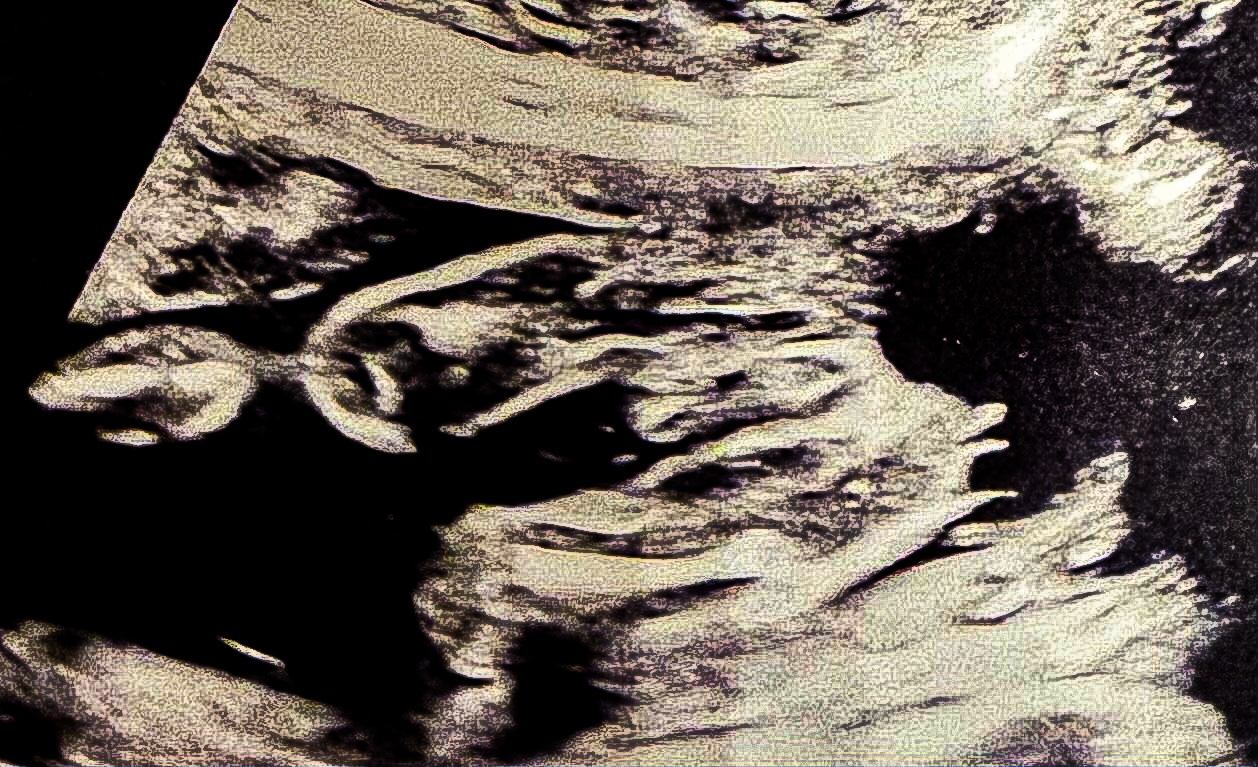

Cześć dziewczyny, chciałam Was zapytać co sądzicie na temat płci? Raz mówią, że syn, raz że córka. Cały czas pępowina między nogami więc nie ma tej pewności.

Zdjęcie USG z 19+1 ☺️